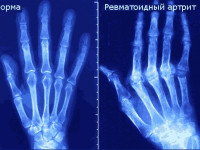

Более 31 миллионов американцев страдают от артрита. Существуют два основных типа артрита: ревматоидный артрит и остеоартрит. Оба влияют на суставы, вызывая боль и отек, а также ограничение движения. Ревматоидный артрит (РА) ...